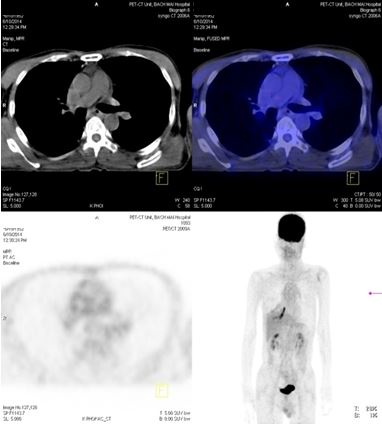

+ Chụp PET/ CT đánh giá lại sau 4 tháng điều trị.

- Trước điều trị: Khối u 2,4x1,7cm, max SUV=8,50. Hạch dưới carina KT 3,1x3,5cm, max SUV=10,29

- Sau điều trị 4 thángKhông rõ u, không có hạch trung thất

Trước điều trị: Hạch thượng đòn phải 1,1cm, max SUV=5,67; Hạch thượng đòn trái 0,8cm, max SUV=3,97.

Sau điều trị: Không thấy hạch thượng đòn

Trước điều trị: Tổn thương cung sau xương sườn số 2 bên phải, giá trị max SUV=3,13.

Sau điều trị 4 tháng: Không có bất thường

Trước điều trị: Hạ phân thùy VI gan P có nốt 1,2cm, max SUV= 4,15. Hạch ổ bụng: 8,5x5,1 cm  max SUV=10,45

Sau điều trị 4 tháng: Không có tổn thương

Đánh giá sau 4 tháng điều trị: Bệnh nhân đáp ứng hoàn toàn, lâm sàng cải thiện tốt, khối u và các hạch, cơ quan khác di căn tan biến. Tuy nhiên, trong quá trình bệnh nhân sử dụng thuốc, xuất hiện nổi ban ngoài da vùng mặt, ngực mức độ nhẹ. Bệnh nhân tiếp tục được duy trì Iressa 250 mg uống 1 viên / ngày.